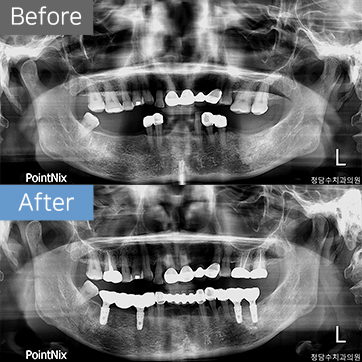

임플란트 60대여 임플란트

60대여 임플란트